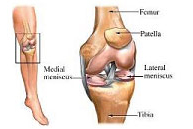

La articulación de la rodilla está formada por las partes inferior del fémur, superior de la tibia y posterior de la rótula actuando como una gran bisagra. Es la articulación más lesionada en el deportista y su tratamiento exige un gran conocimiento de la anatomía así como de la cirugía traumatológica, protésica y artroscópica.

Fracturas de rótula

Las fracturas de rótula representan el 1% de todas las fracturas del esqueleto. Son doblemente más frecuentes en la mujer que en el hombre y, sobre todo, entre la tercera y quinta década de la vida. El impactode la rodilla en flexión sobre el suelo suele ser el mecanismo de producción habitual aunque en otras ocasiones se debe a una contracción brusca del cuádriceps. El hematoma y la imposibilidad para mover la rodilla hacen sospechar el diagnóstico que se confirma radiológicamente con una proyección lateral. El tratamiento de las fracturas de rótula se ha beneficiado de los avances en traumatología mínimamente invasiva pudiendo ser resueltas a través de pequeñas incisiones en la piel gracias a la ayuda de la artroscopia.

Lesiones ligamentosas de rodilla

Las lesiones ligamentosas de la rodilla tienen lugar fundamentalmente en la práctica deportiva aunque también pueden aparecer, y por ello deben descartarse, en el contexto de un politraumatismo. Obedecen generalmente a mecanismos de torsión y/o desviación femoral con la tibia fija en el suelo dando lugar a la rotura. Los deportes habituales de este tipo de lesiones son: futbol, esquí, baloncesto, voleibol, balonmano, artes marciales, deportes de raqueta, patinaje y rugby. Es realmente difícil la exploración clínica tras el traumatismo inicial debido a la inflamación y dolor en la rodilla por lo que en ocasiones una sedación anestésica puede ser de gran ayuda a tal efecto. Finalmente las técnicas de imagen y el estudio artroscópico completarán el estudio diagnóstico. El tratamiento de las lesiones ligamentosas de rodilla depende de diversos factores como la edad del paciente y el tipo de estructuras implicadas en la lesión. Generalmente, aquellas lesiones que producen inestabilidad o bloqueo de la rodilla reciben tratamiento artroscópico y rehabilitación posterior para recuperar la función normal de la rodilla.